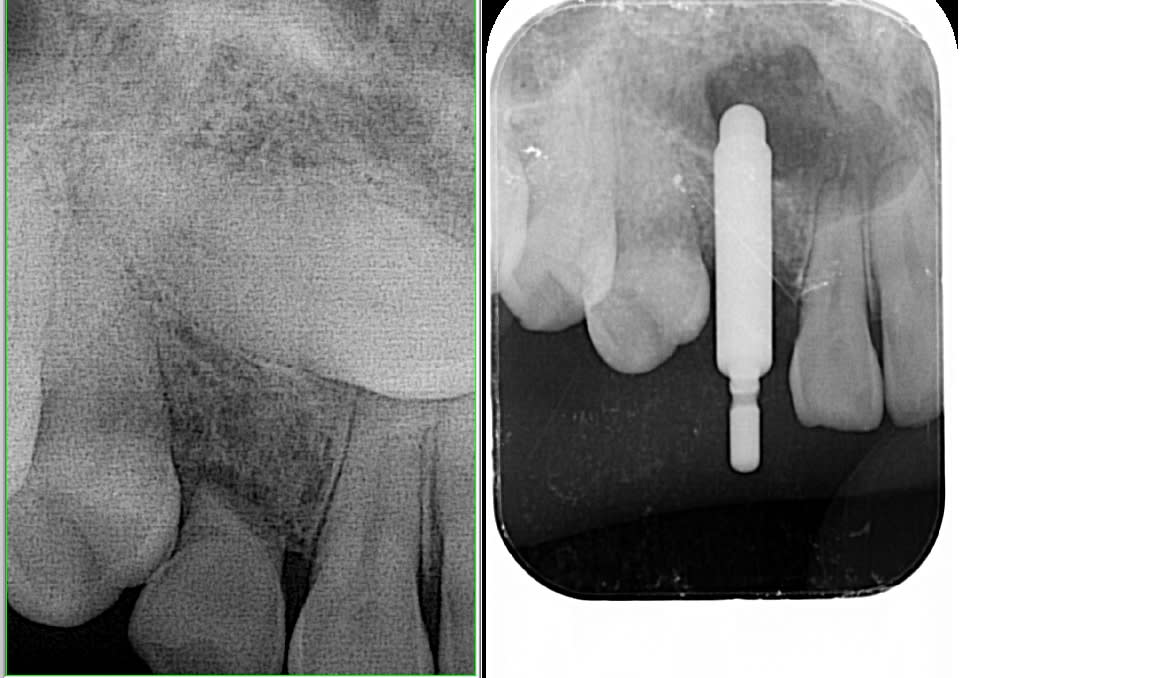

Dent extraite et implant posé